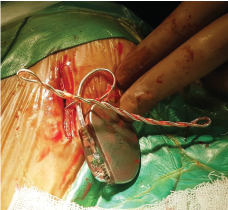

The patient was again admitted with one episode of syncope and twitching in the right upper quadrant of the abdomen. Electrocardiogram showed atrial fibrillation with a ventricular rate of 36/minute. A pulsation in her abdomen due to diaphragmatic stimulation was observed. Temporary pacemaker lead was inserted through the right femoral route and connected to the pulse generator. Fluoroscopy showed twisted ventricular lead and its retraction into the right atrium (Figure 1 and Figure 2). A diagnosis of pacemaker Twiddler's syndrome was made. Under all aseptic precautions, the pacemaker pocket was immediately reopened. The condition of the lead just after opening the pocket and after uncoiling is shown (Figure 3 and Figure 4). A new active fixation screwing ventricular lead was inserted at the right ventricular apex. The parameters were checked, R wave, the threshold, and lead impedance were 14 mV, 0.5 V, and 700 ohms, respectively. The pulse-generator was fixed on the pectoral muscle with non-absorbable suture. Postoperative hospital stay was uneventful, and the patient was asymptomatic at subsequent follow-ups..

Figure 3: The condition of the ventricular lead after opening the pacemaker pocket. The lead is twisted multiple times on itself. View Figure 3